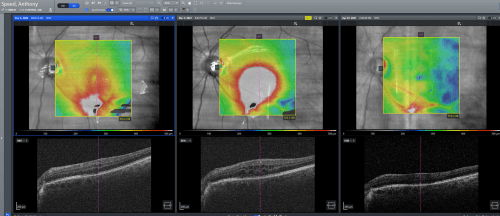

Where am I now? A little over a month ago at the end of March, I underwent a third operation, this time to remove the oil in my eye and replace it with gas again. This had always been planned, but became more urgent due to the oil causing my retina to become inflamed. We had tried steroid drops to control and reduce the inflammation a month prior but as the photo below shows this was not successful, so back under the knife again.